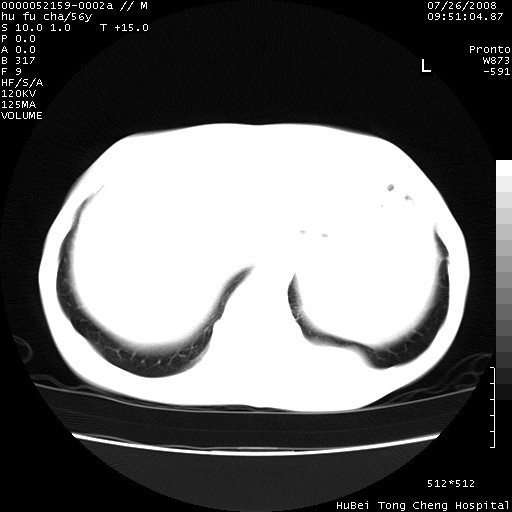

以下是引用zsl6918在2008-8-25 22:47:00的发言:[br]胸骨,胸椎及肋骨均可见多发转移表现,肝内低密度结节不除外转移。原发灶可能在右肺。双侧可见支扩表现。